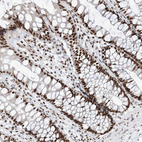

Immunohistochemical staining of human colon shows strong nuclear positivity in glandular cells.